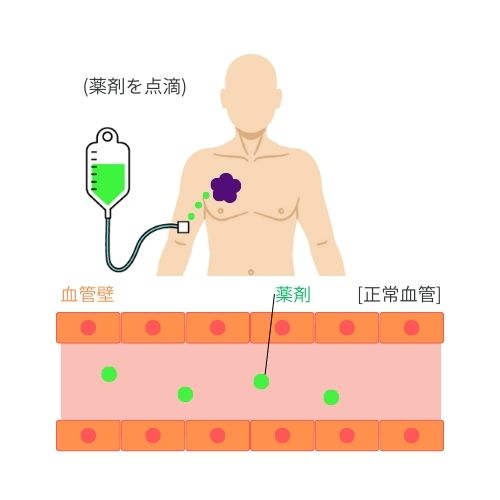

➀ 薬剤を点滴

治療の初めの重要なステップとして、患者様には特定の薬剤が点滴によって投与されます。

この薬剤は血管を通じて体内を流れ、ターゲットとなるがん細胞を目指します。

この薬剤は光感受性を持っており、後に行われる光照射治療で重要な役割を果たします。